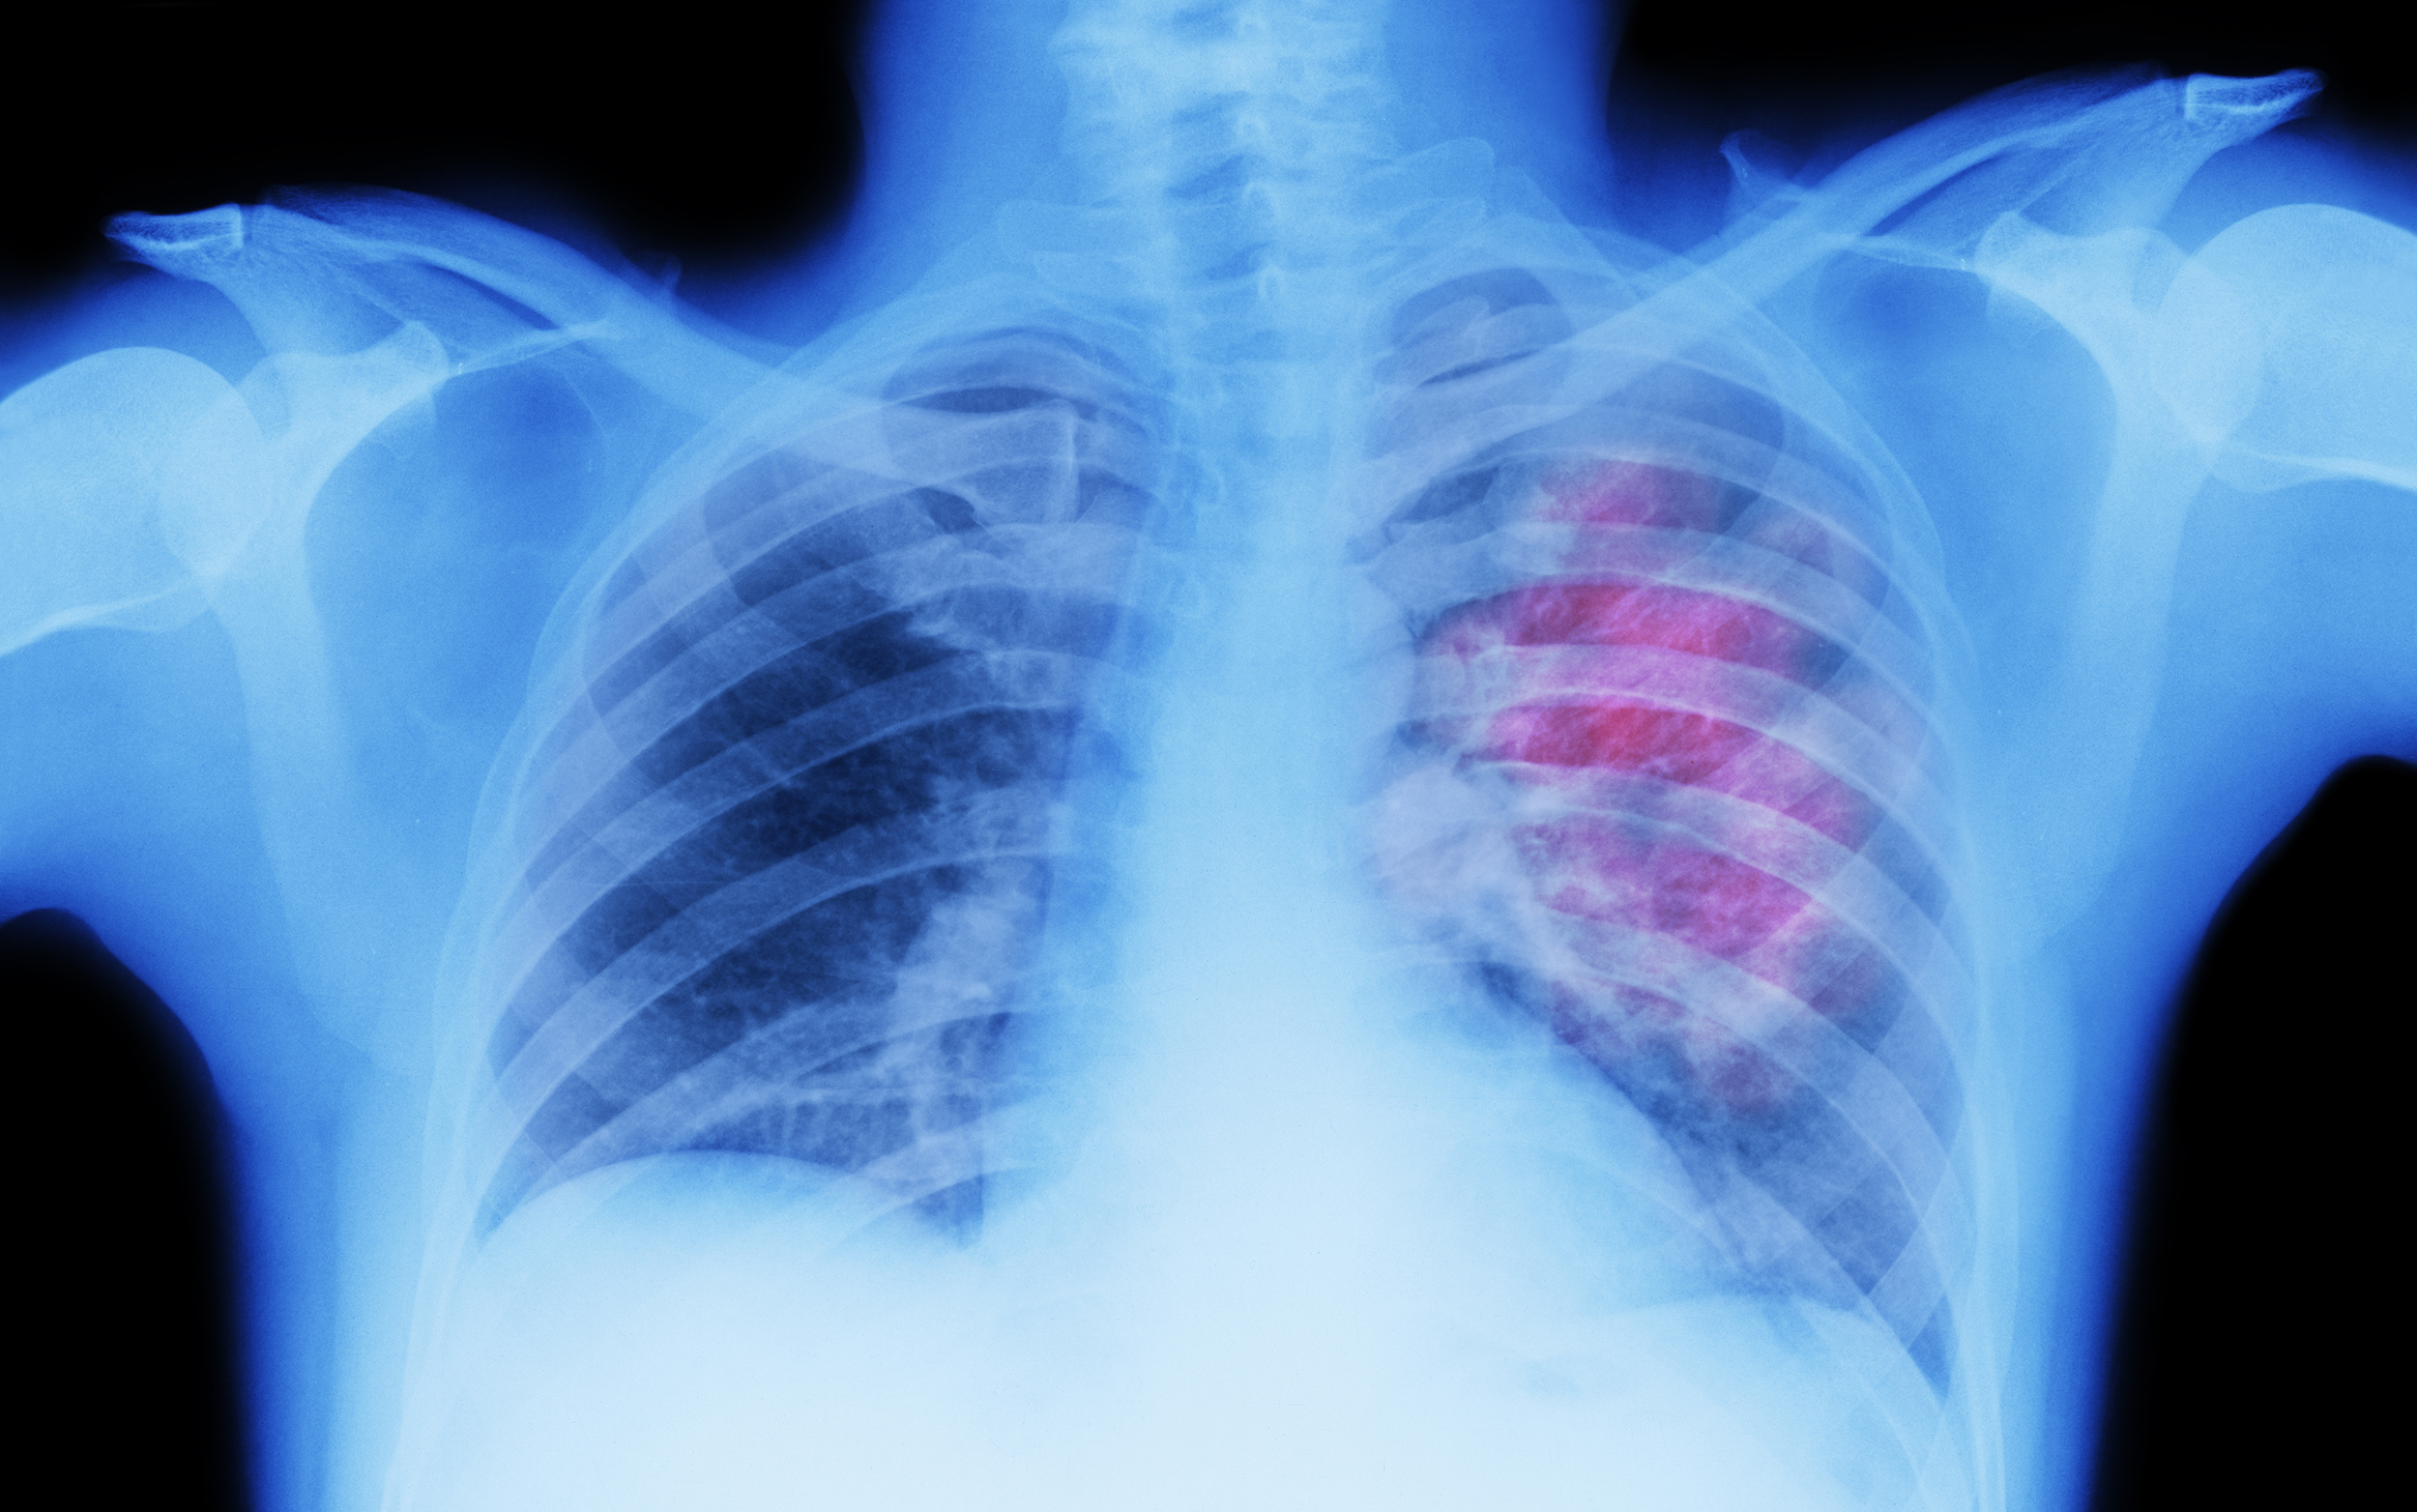

En la actualidad, esta enfermedad sigue siendo la principal causa de muerte a nivel mundial. Específicamente en Colombia, para el año 2022, se identificaron 117.620 nuevos casos y 56.719 muertes por esta causa. Además, según datos de Globocan de 2022, el cáncer de próstata, de pulmón y el mieloma múltiple son algunos de los cánceres con mayor impacto en el país, ya que, durante los últimos 5 años han tenido unas altas tasas de prevalencia.

Por ejemplo, el cáncer de próstata tuvo 39.839 casos, el cáncer de pulmón 8.936 casos y el mieloma múltiple 3.843 casos, que, en comparación con el periodo de 2015, los casos nuevos, los prevalentes y las defunciones han aumentado en 57%, 120% y 222%, respectivamente. Cada una de estas enfermedades requiere de un abordaje individual, según el tipo de patología, el estadio de la enfermedad y las características específicas del paciente.

Con este tipo de tratamientos, los resultados han demostrado ser alentadores al prolongar los tiempos de supervivencia libre de enfermedad y aumentar la duración de la respuesta de la terapia, lo que de manera consecuente llevaría a una mejor calidad de vida, experimentando menos complicaciones y hospitalizaciones. Esto le permite al paciente realizar sus actividades del día a día, aumentar su productividad y reducir los costos de la atención médica. Estas opciones son eficaces y tolerables para pacientes con ciertos tipos de cáncer como el de pulmón o linfoma.